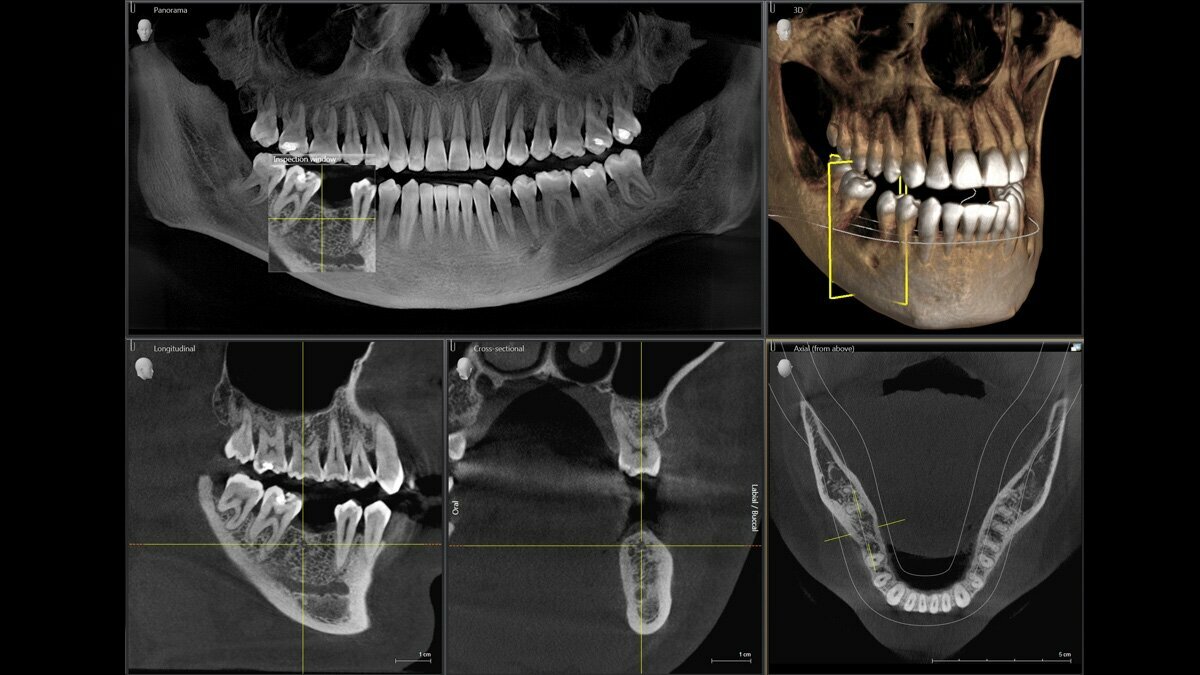

Gold Dent специализируется на различных направлениях стоматологии: общей терапии, хирургии, ортодонтии, эстетической и детской стоматологии, имплантологии, протезировании и эндодонтии. В клинике применяются передовые технологии, такие как цифровая стоматология CAD/CAM, лечение под микроскопом, компьютерная томография и костная пластика.

Если вы на самом деле хотите найти место с достойным сервисом, хорошими врачами, нормальным подходом к клиенту, то вам сюда. На первой консультации мне сразу же предложили сделали 3Д снимок челюсти, и провели консультацию по каждому зубу. У них в кабинете стоит компьютер, на который они мне вывели ЗД снимок моей челюсти, показали все проблемные зубы, объяснили что может случиться, если не вылечить их в самое ближайшее время. Стоимость лечения каждого зуба сказали сразу. Сразу понятно что мне лечат и зачем. Однозначно рекомендую эту клинику.